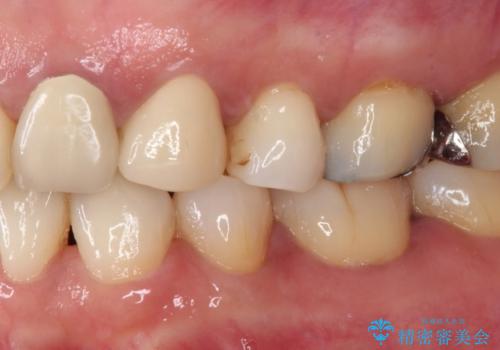

著しい八重歯であったそうで、一般的に抜歯を行う第一小臼歯ではなく八重歯を抜歯して矯正治療を行ったとのことでした。

補綴治療では歯の形態を犬歯に近づけ、将来的な歯根への負担を軽減できるようにしました。

補綴後6ヶ月経過しレントゲンを撮影したところ、歯根周辺に病変認められず、良好な経過をたどっていることが分かりました。